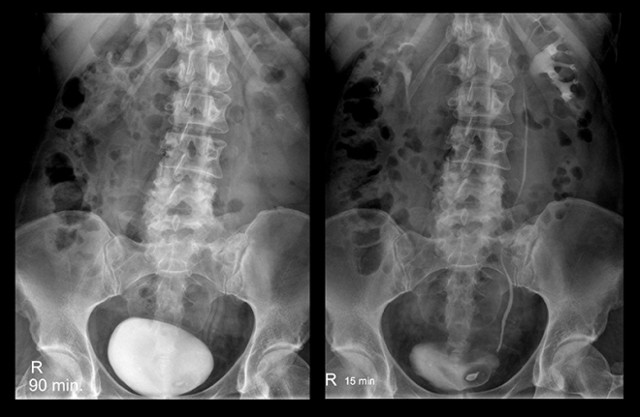

Цистография — это особый рентген мочевого пузыря. Метод основан на введении в этот орган контрастного вещества, после чего при помощи рентгеновских лучей выполняется серия снимков.

Чаще всего рентгеноконтрастный препарат вводится снизу вверх, через уретру.

Наполненные контрастом органы хорошо видны на рентгеновских снимках, что позволяет судить об их размерах и очертаниях, наличии посторонних включений.

Процедура имеет большое значение для диагностики пузырно-мочеточникового рефлюкса — явления, при котором происходит обратный заброс мочи из мочевого пузыря вверх, в мочеточник. Эту патологию во время цистографии можно выявить даже в состоянии покоя. Особенно часто она наблюдается на отсроченных цистограммах. В этом случае снимки делаются каждые 30 минут в течение 3 часов.

Восходящий рентген мочевого пузыря у детей с контрастом выполняется в следующем порядке:

- С помощью эластичного резинового катетера опорожняют мочевой пузырь. При введении катетера новорожденным мальчикам берут инструмент, используемый для катетеризации мочеточников.

- Через этот же катетер орган наполняют жидким контрастным веществом. Детям до 2 лет вводят 50 мл раствора, в 5-7 лет — 80-100 мл, а после 7 лет — 100-150 мл. В этот момент ребенок может испытывать боль.

- Заполнив пузырь, катетер осторожно извлекают.

- Делают несколько снимков в 3 проекциях: осевой, переднезадней и полубоковой.

- Ребенок мочится самостоятельно, после этого выполняют снимок пустого пузыря.

В ряде случаев, когда цистография предполагает одновременное обследование пузыря, почек и мочеточников, может понадобиться внутривенное введение контраста. С током крови вещество попадает в почки, а уже из них вместе с уриной — в мочевой пузырь, после чего ребенок готов к выполнению рентгеновских снимков.

Врач-уролог изучает снимки ребенка, полученные при рентгене мочевого пузыря. В норме наполненный орган у детей имеет четкие контуры и грушевидную форму. Восходящая цистография помогает выявить: